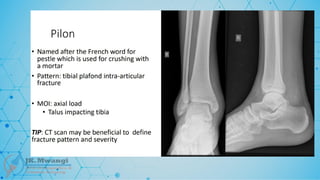

Fracture Eponyms

Q & A

TAKE AWAY

Introduction

What is a bone?

A highly vascularized, living, constantly

changing mineralized connective tissue